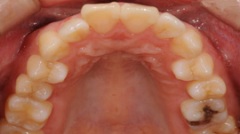

審美的治療の実例

出っ 歯が気になって来院した患者様です。海外に行くことが決まっていたので、矯正治療をするだけの時間の余裕がありませんでした。そこで、上の前歯4本をオー ルセラミッククラウンに変えました。いかがですか?どれが人口の歯か見分けがつきません。患者様ご本人も大満足してくださいました。

当院では咬み合わせ、歯列のみならず、歯肉との調和も考慮し治療にあたります。自然さを追求し、治療した後も結果を長く安定させるように、しっかりとメインテナンスサポート致します。

| Before | After |